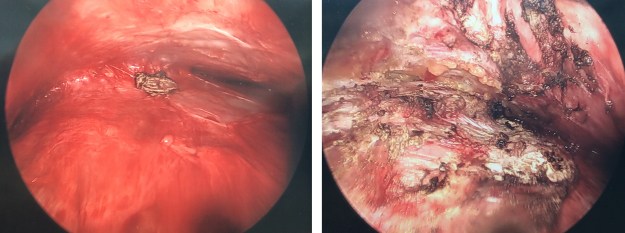

During my follow up appointment with Dr. M we discussed the reason for this: with nothing separating the pec muscle and my ribs, the tissue on my left breast adhered to them. This wasn’t a surprise, but Dr. M had to do some extra work to prep the pocket again. He went in through my armpit to avoid messing with the incision site that gave us necrosis and later the breakdown that caused an infection. He shared photos he took during the procedure illustrating the adhesion and how he separated and cauterized it:

This helps explain why my left side hurts so darn much! In addition to the internal sculpting, I also have a large incision and the drain tube in my armpit. Doing my best to not move my left arm! I’m still Norco-ing it up every six hours and the drain has been kicking out close to 100mL/day. I went in on Friday with the expectation that I’d be leaving it behind, but at this rate, I’m not sure we’ll be able to remove it when I go back on Monday.